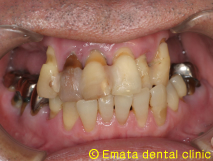

患者様は元々入れ歯をつかったことがありません。上顎6歯が歯周病が進行し残念ですがすべて抜歯です。年齢的(60歳)にも仕事上からも、総入れ歯は絶対いやだということで、All-on-4によりその日で固定式の仮歯を入れる手術をおこないました。

治療前